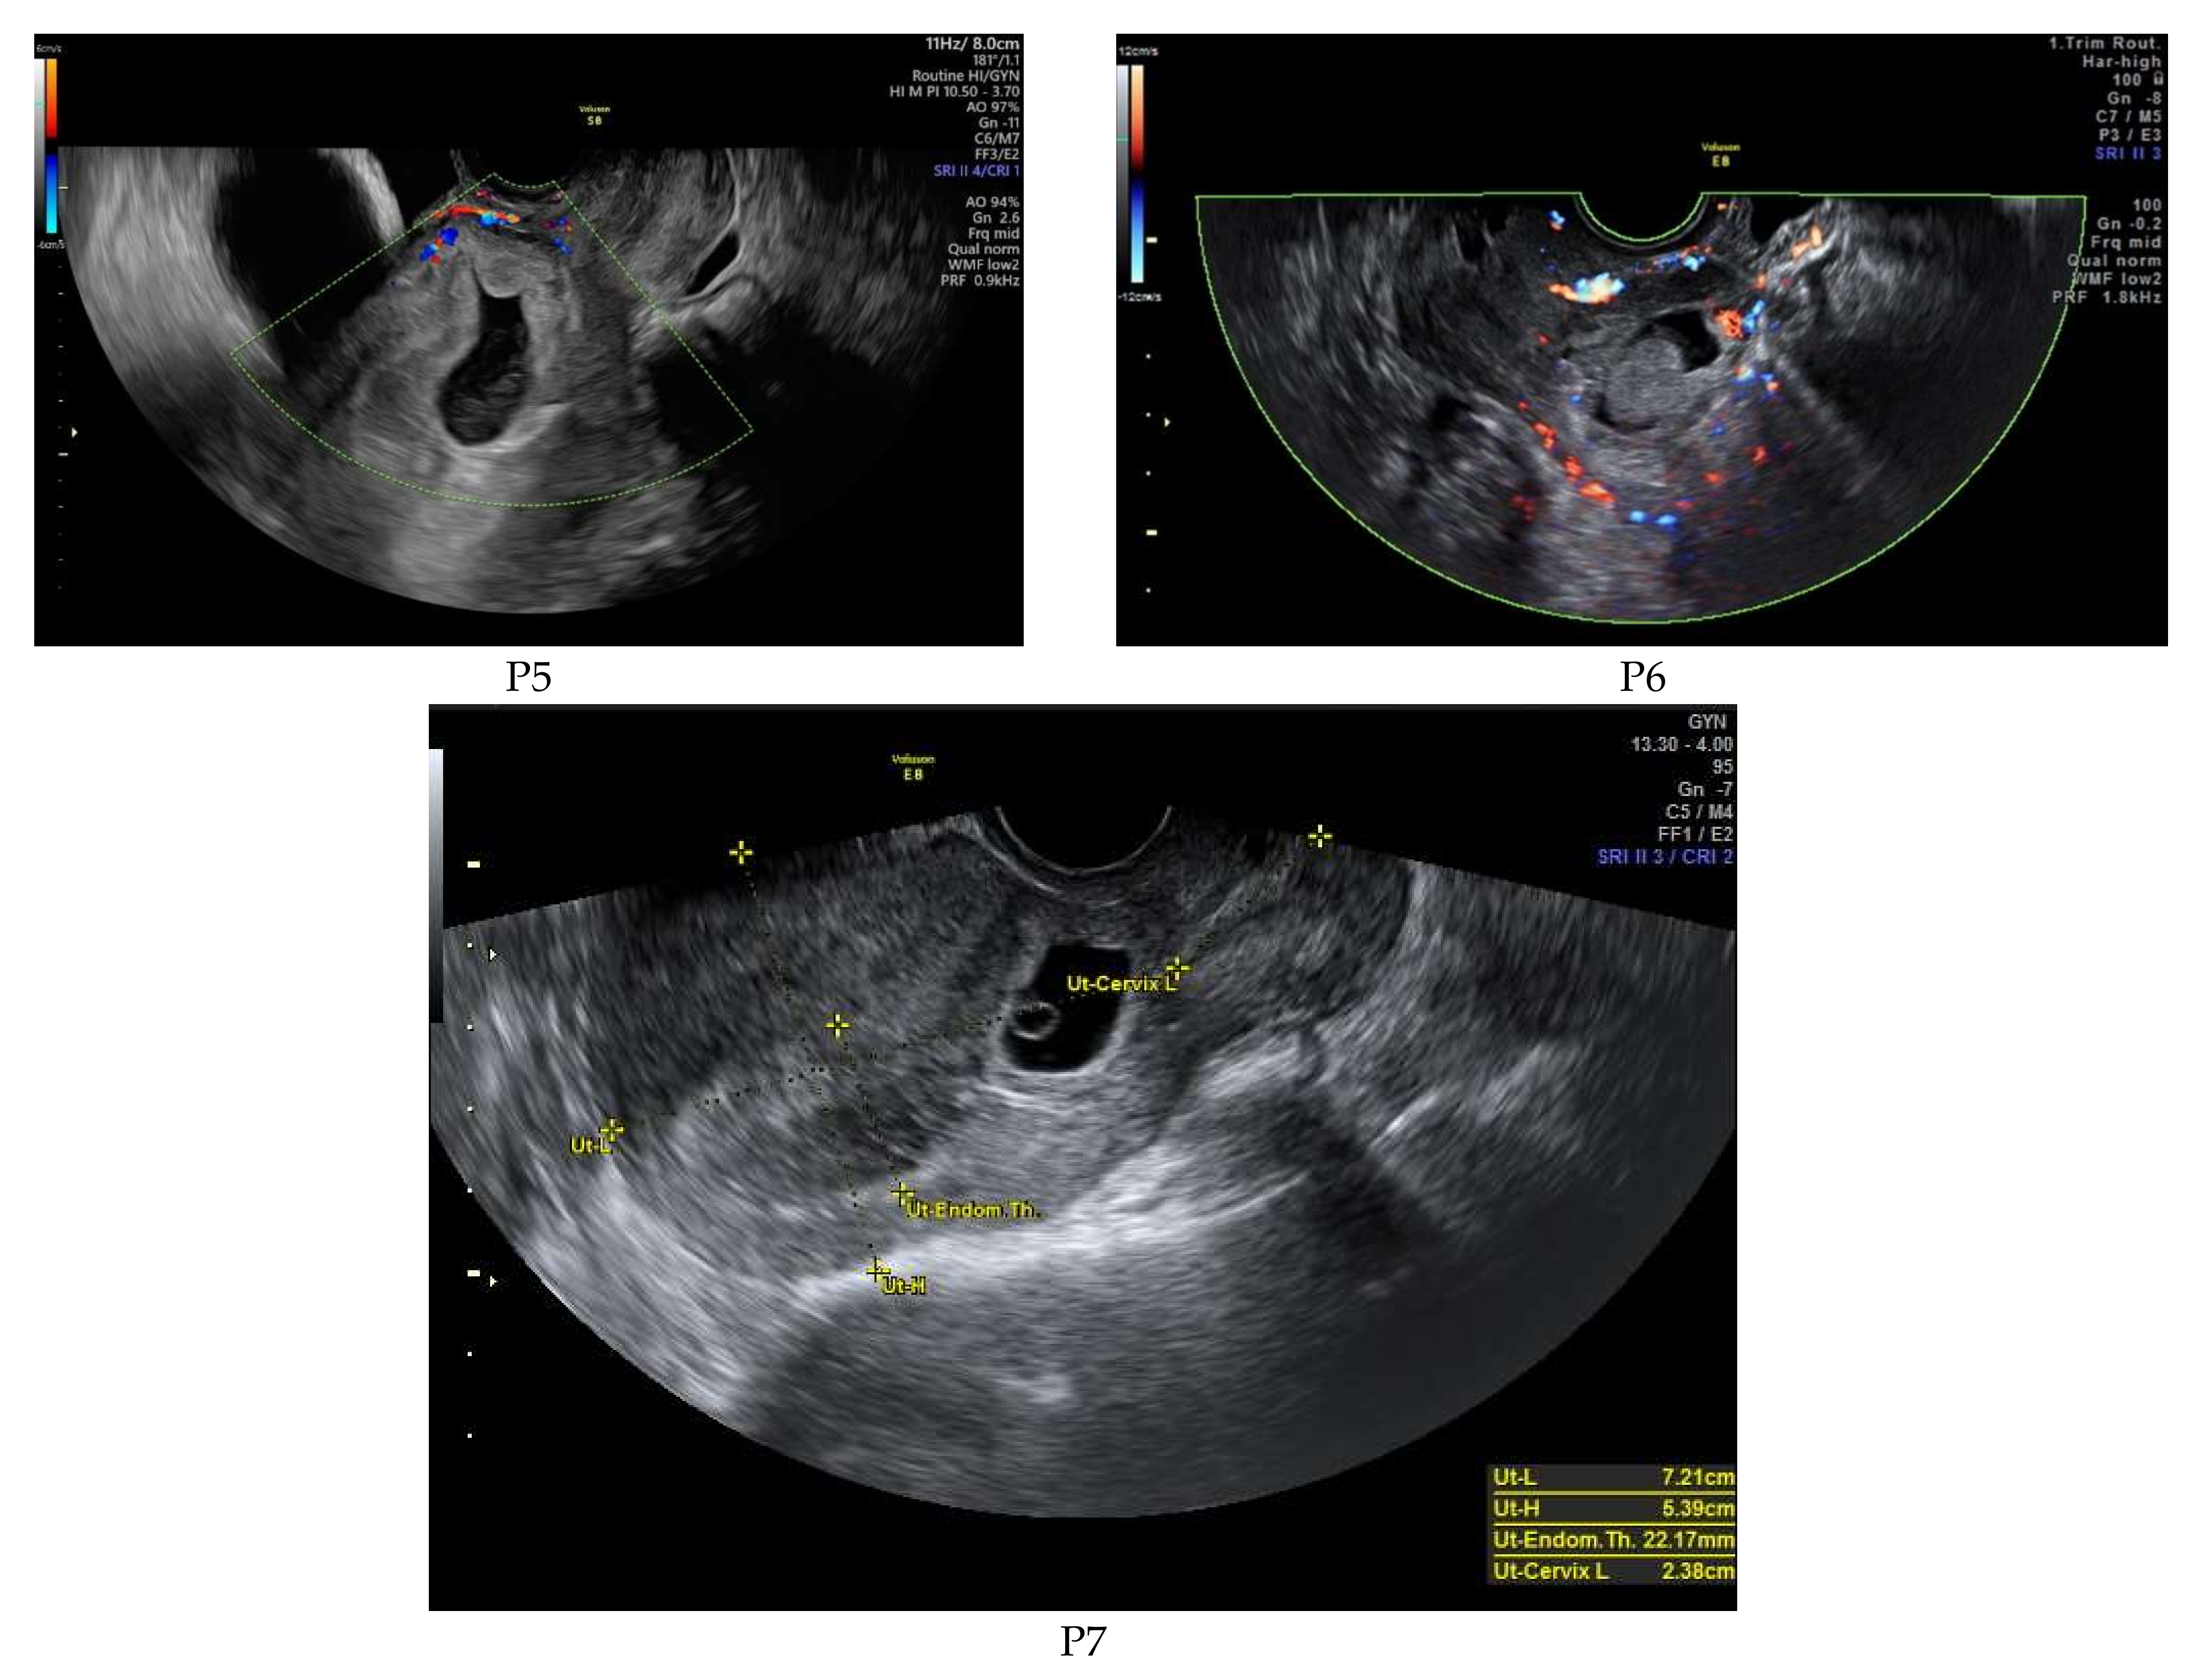

| Patient No | Peak bHCG Value | Gestational Age | CSP | Treatment Course | Outcome |

|---|---|---|---|---|---|

| P1 * | 99,999 | 7w + 1d | Type 1 | 1. Intramuscular methotrexate injection 2. Uterine artery embolization 3. Suction evacuation | No complications |

| P2 | 99,999 | 5w + 2d | Type 2 | 1. Intramuscular methotrexate injection 2. Uterine artery embolization 3. Suction evacuation | No complications |

| P3 | 62,309 | 7w + 2d | Type 2 | 1. Intramuscular methotrexate injection 2. Uterine artery embolization 3. Suction evacuation | No complications |

| P4 | 5938 | 5w + 5d | Type 1 | 1.Intramuscular methotrexate injection 2. Suction evacuation | No complications |

| P5 | 4579 | 5w + 6d | Type 2 | 1.Intramuscular methotrexate injection 2. Uterine artery embolization 3.Suction evacuation | No complications |

| P6 | 70,373 | 6w + 5d | Type 1 | 1. Intramuscular methotrexate injection 2. Uterine artery embolization 3. Suction evacuation | No complications |

| P7 | 46,317 | 6w + 2d | Type 2 | 1. Intramuscular methotrexate injection 2. Uterine artery embolization 3. Suction evacuation | No complications |

| Patient No | Residual Myometrium Thickness (mm) | Fetal Heartbeat | Vascularization | Crown-Rump Length (mm) | Gestational Sac Diameter (mm) | BMI |

|---|---|---|---|---|---|---|

| P1 * | 2 | absent | increased | 11 | 22/20 | 27.5 |

| P2 | 2.1 | absent | increased | Not measured | 11 | 22.5 |

| P3 | 1.6 | present | increased | 13 | 24 | 28.4 |

| P4 | 3.3 | absent | normal | 2 | 8 | 33.6 |

| P5 | 4 | absent | normal | Not measured | 8 | 29.4 |

| P6 | 3.8 | absent | increased | 4 | 23 | 19.7 |

| P7 | 3.5 | present | increased | 5 | 28 | 21 |